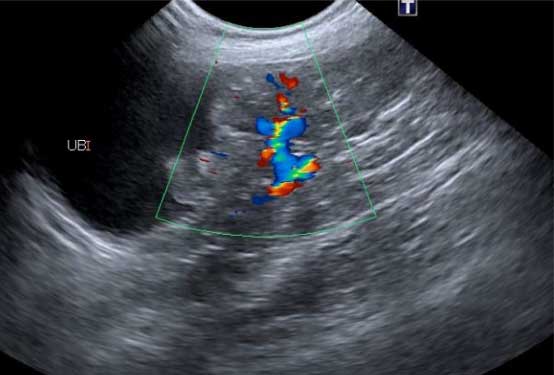

超音波検査

腎臓や膀胱の内部構造を確認します。腎臓においては形態や構造の変化、血流の評価を、膀胱においては壁の厚さや不整、内部の結石や血餅などの評価を行います。その他にも、尿管や尿道、雌では子宮や卵巣、雄は前立腺の評価にも有用です。

超音波腎臓

超音波膀胱